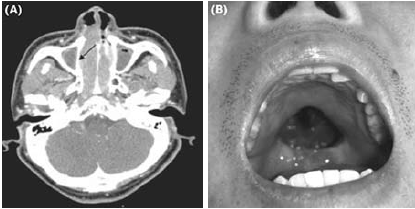

[사진] NK-T세포 림프종 환자의 CT 및 육안 사진